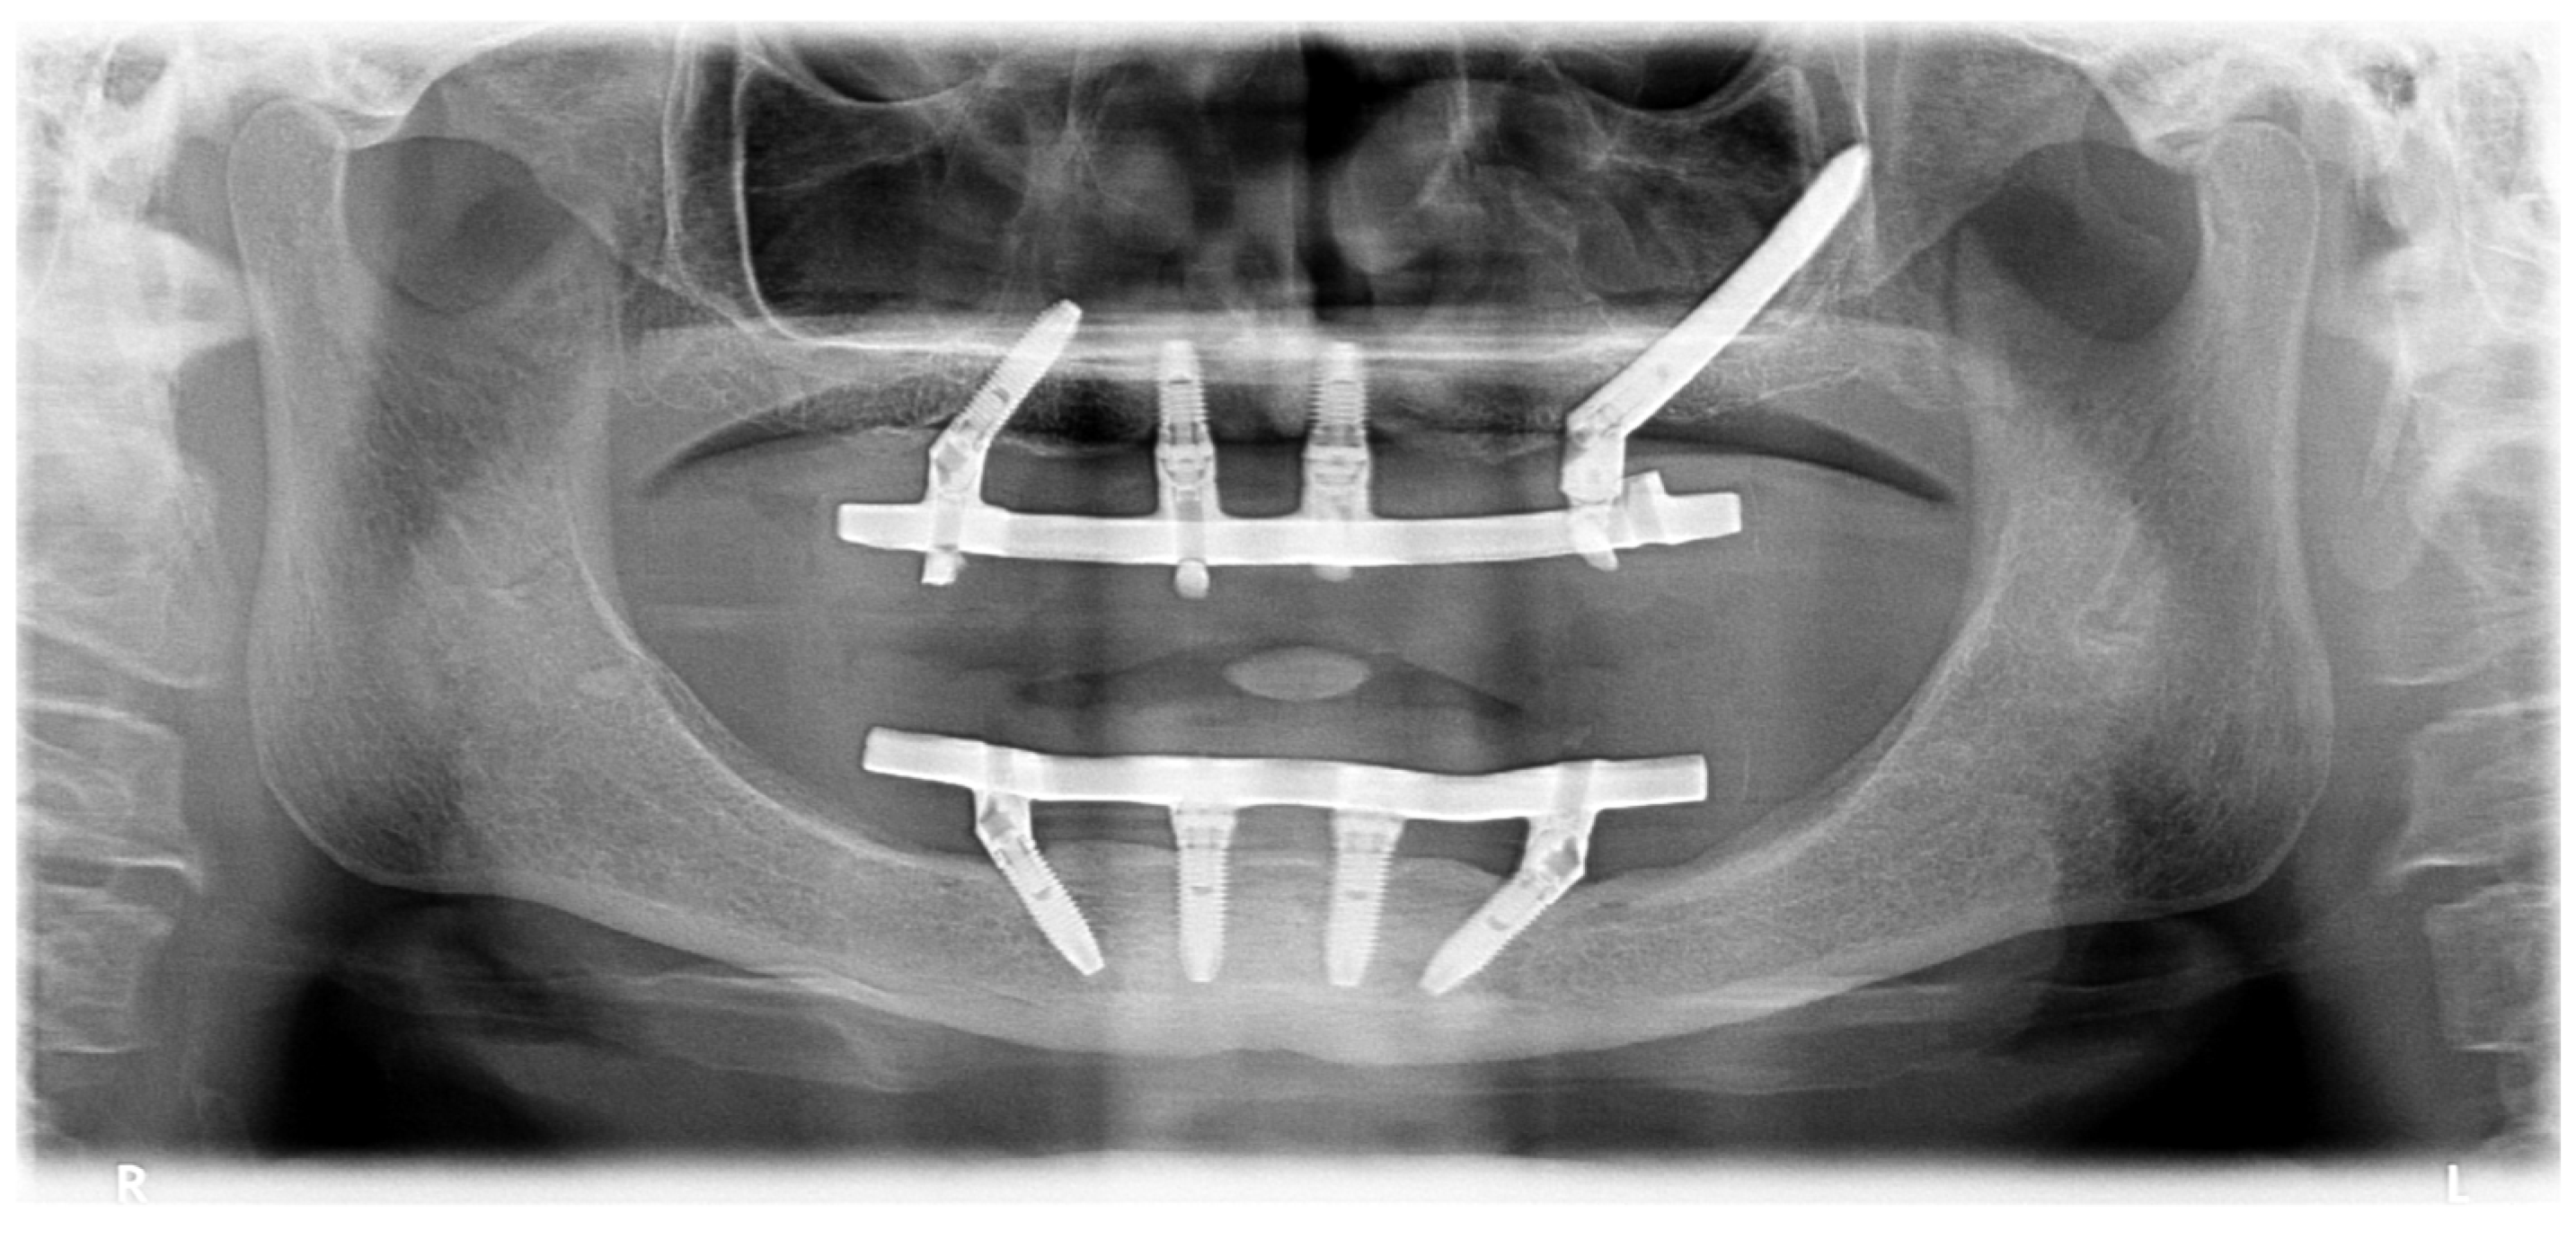

2. Case Reports

2.1. Patient 1

2.2. Patient 2